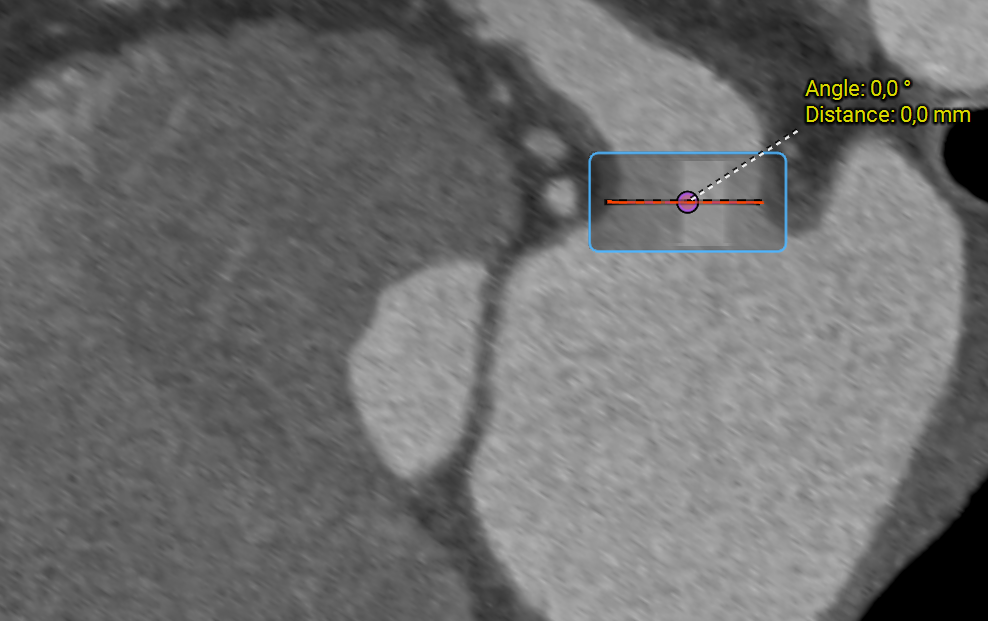

CT vs. 3D TEE

While CT offers superior spatial resolution and reproducibility for complex anatomies, 3D TEE provides real-time dynamic imaging that can be used both before and during the intervention. Many centers now adopt a multimodality approach, combining both modalities for comprehensive evaluation and optimal device selection.

Screenshot 2025-10-07 170109.png